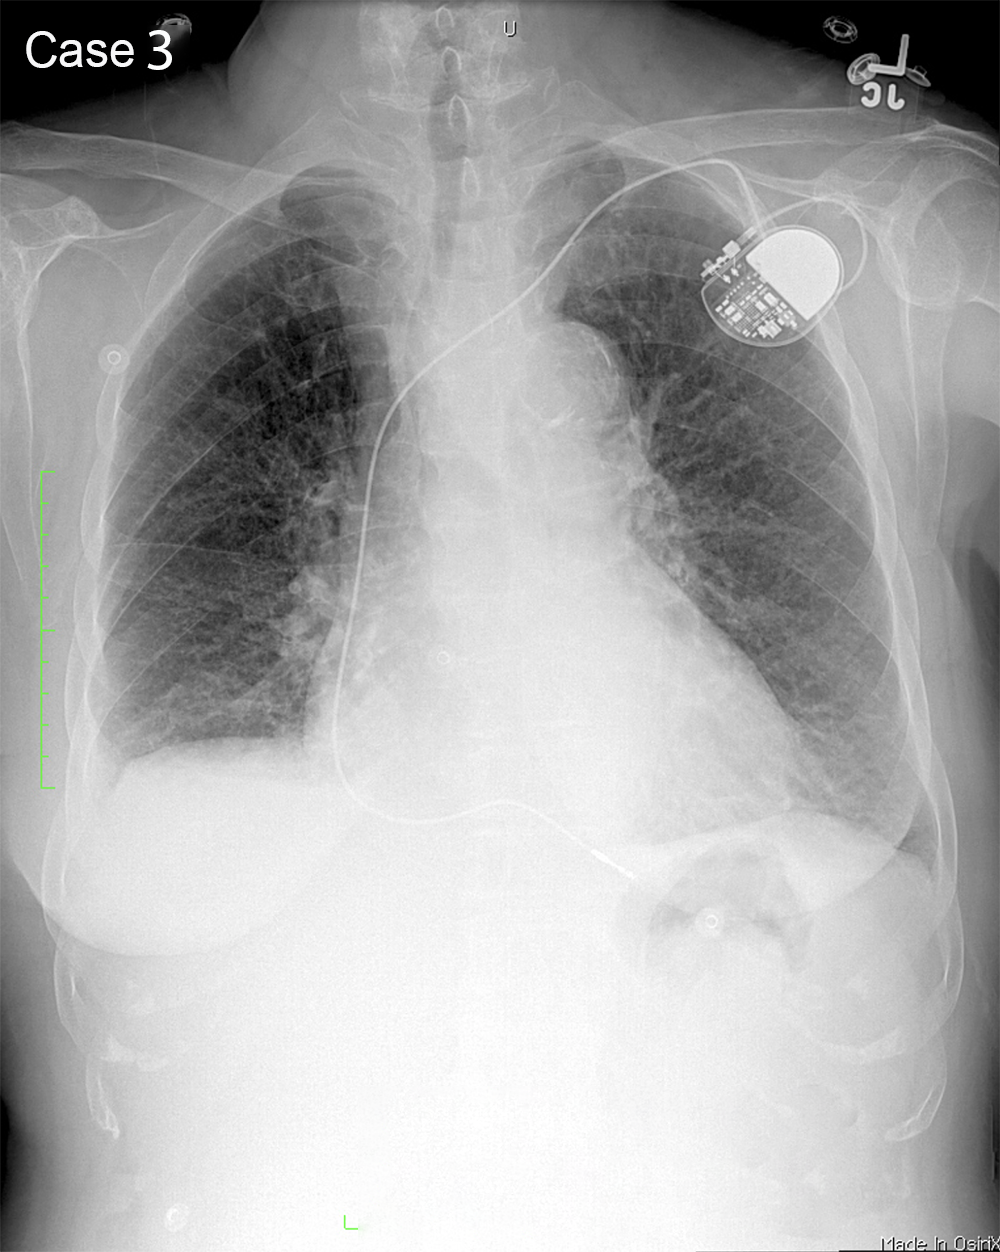

You are given a review of the ABCDE approach to frontal CXR interpretation and five cases to preview before class.

For each of these five cases, try to identify what is most abnormal, using the ABCDE framework to organize your search. Be descriptive! Try not to jump to conclusions regarding the final diagnosis. We will discuss each case in more detail in class. You can also consider what the next imaging study should be, and can make use of the ACR Appropriateness Criteria to help in this decision. You can also search the STR website for educational materials pertinent to each case.